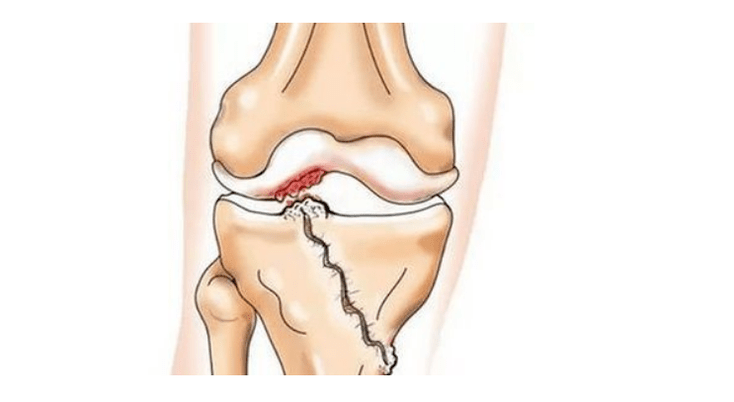

- injuries (fractures, tears of the meniscus and anterior cruciate ligament).Unfortunately, in every person, regardless of age, these injuries lead to excessive stress on the cartilage.A fracture of any part of the bones covered with cartilage is accompanied by the formation of an unevenness - a "step".In this area, during movement, abrasion occurs and arthrosis is formed;

In arthrosis (osteoarthrosis), in addition to the progressive destruction of cartilage, the loss of its elasticity and shock-absorbing properties, the bones are gradually involved in the process.When loaded, sharp edges (exostoses) appear, which are mistakenly considered "salt deposits" - in classic arthrosis, salt deposits do not occur.As arthrosis progresses, it continues to "eat" the cartilage.Then the bone is deformed, cysts form there, all the structures of the joint are affected and the leg bends.

Absence of cartilage in most affected areas, severe sclerosis (hardening) of the bone, many osteophytes, and sharp narrowing or absence of the joint space.The pain is almost constant, the gait is impaired.Mobility is sharply limited and deformation of the joint is noticeable.NSAIDs, physical therapy and other standard methods of treating knee osteoarthritis are ineffective.